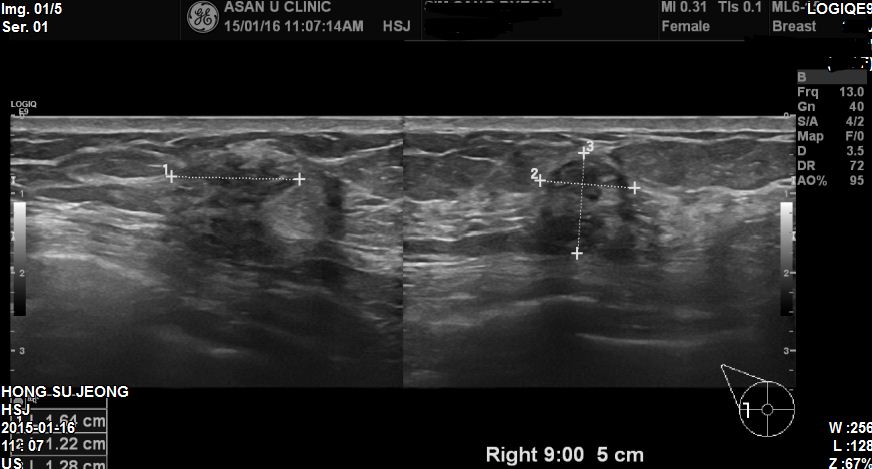

건진상 이상소견으로 내원하신 68세 환자분이십니다.

본원에서 우측 9시방향에 1.64cm 혹 조직검사 시행하였고

상피내암 진단되었습니다.